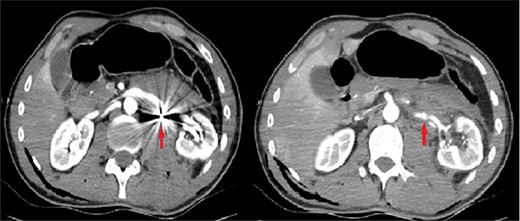

A 26-year-old male patient was brought to the emergency department due to a gunshot wound. He was hemodynamically stable; however, hematuric urine output was observed. In complete blood count, hemoglobin (Hb) and hematocrit (Hct) values were detected as 12.6 g/dl and 39.4%. The abdominopelvic computed tomography (CT) showed minimal laceration in liver segment 6, left retroperitoneal hematoma and two bullet cores adjacent to the left renal artery and lower pole of the left kidney. A CT angiography (CTA) was performed. This investigation revealed a bullet core and a 4-mm RAP in the middle of the left renal artery (Fig. 1).

The initial computerized tomographic angiography image of the bullet core adjacent to the middle segment of the left renal artery and the renal pseudoaneurysm.